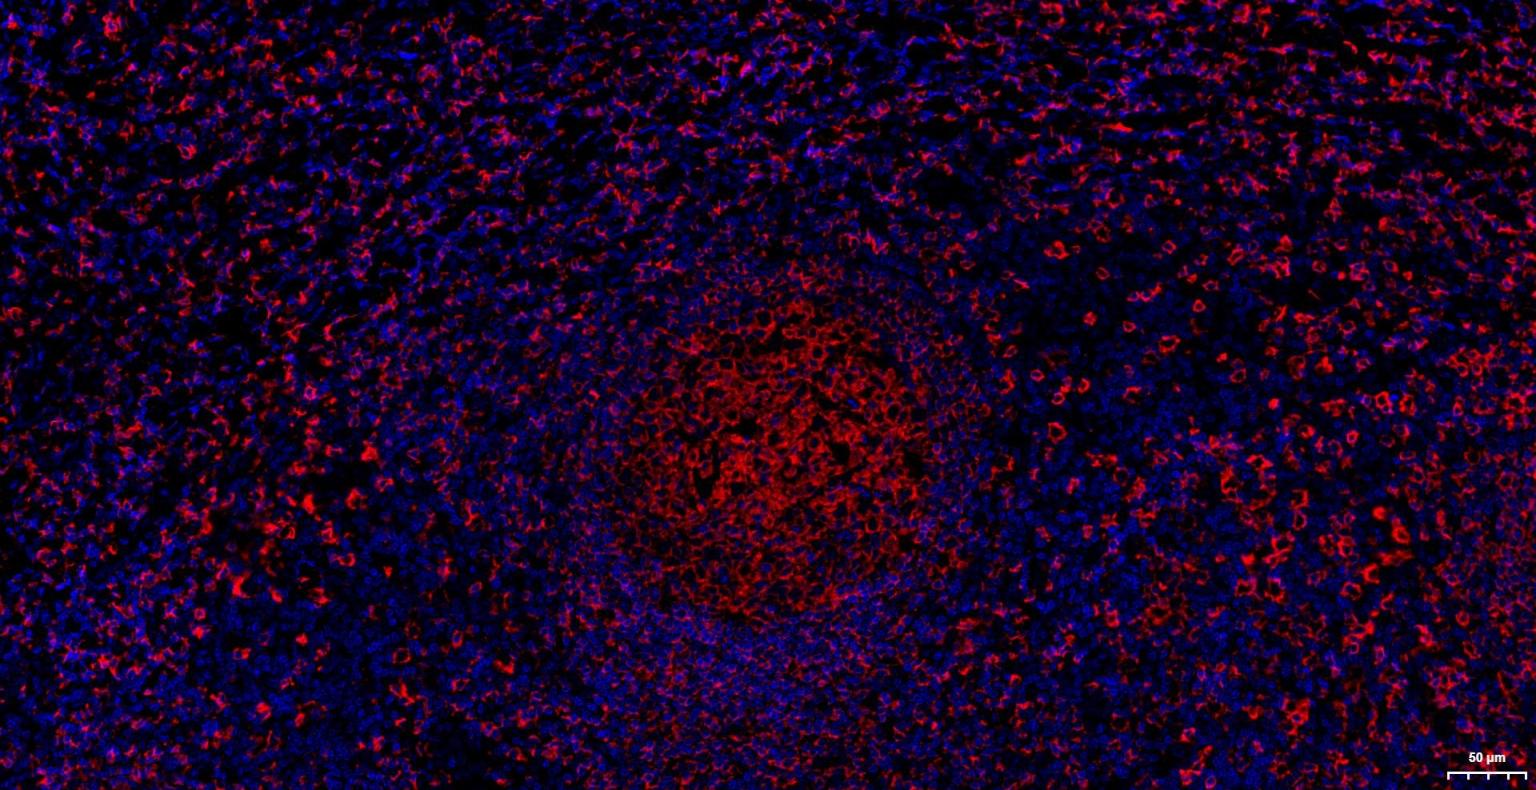

Paraformaldehyde-fixed, paraffin embedded Human Tonsil; Antigen retrieval by boiling in sodium citrate buffer (pH6.0) for 15 min; The section was incubated with CD20 Monoclonal Antibody, Unconjugated (bsm-63327R) at 1:200 overnight at 4°C. Followed by conjugated Goat Anti-Rabbit IgG antibody (Red, bs-0295G-BF594), DAPI (blue, C02-04002) was used to stain the cell nuclei.